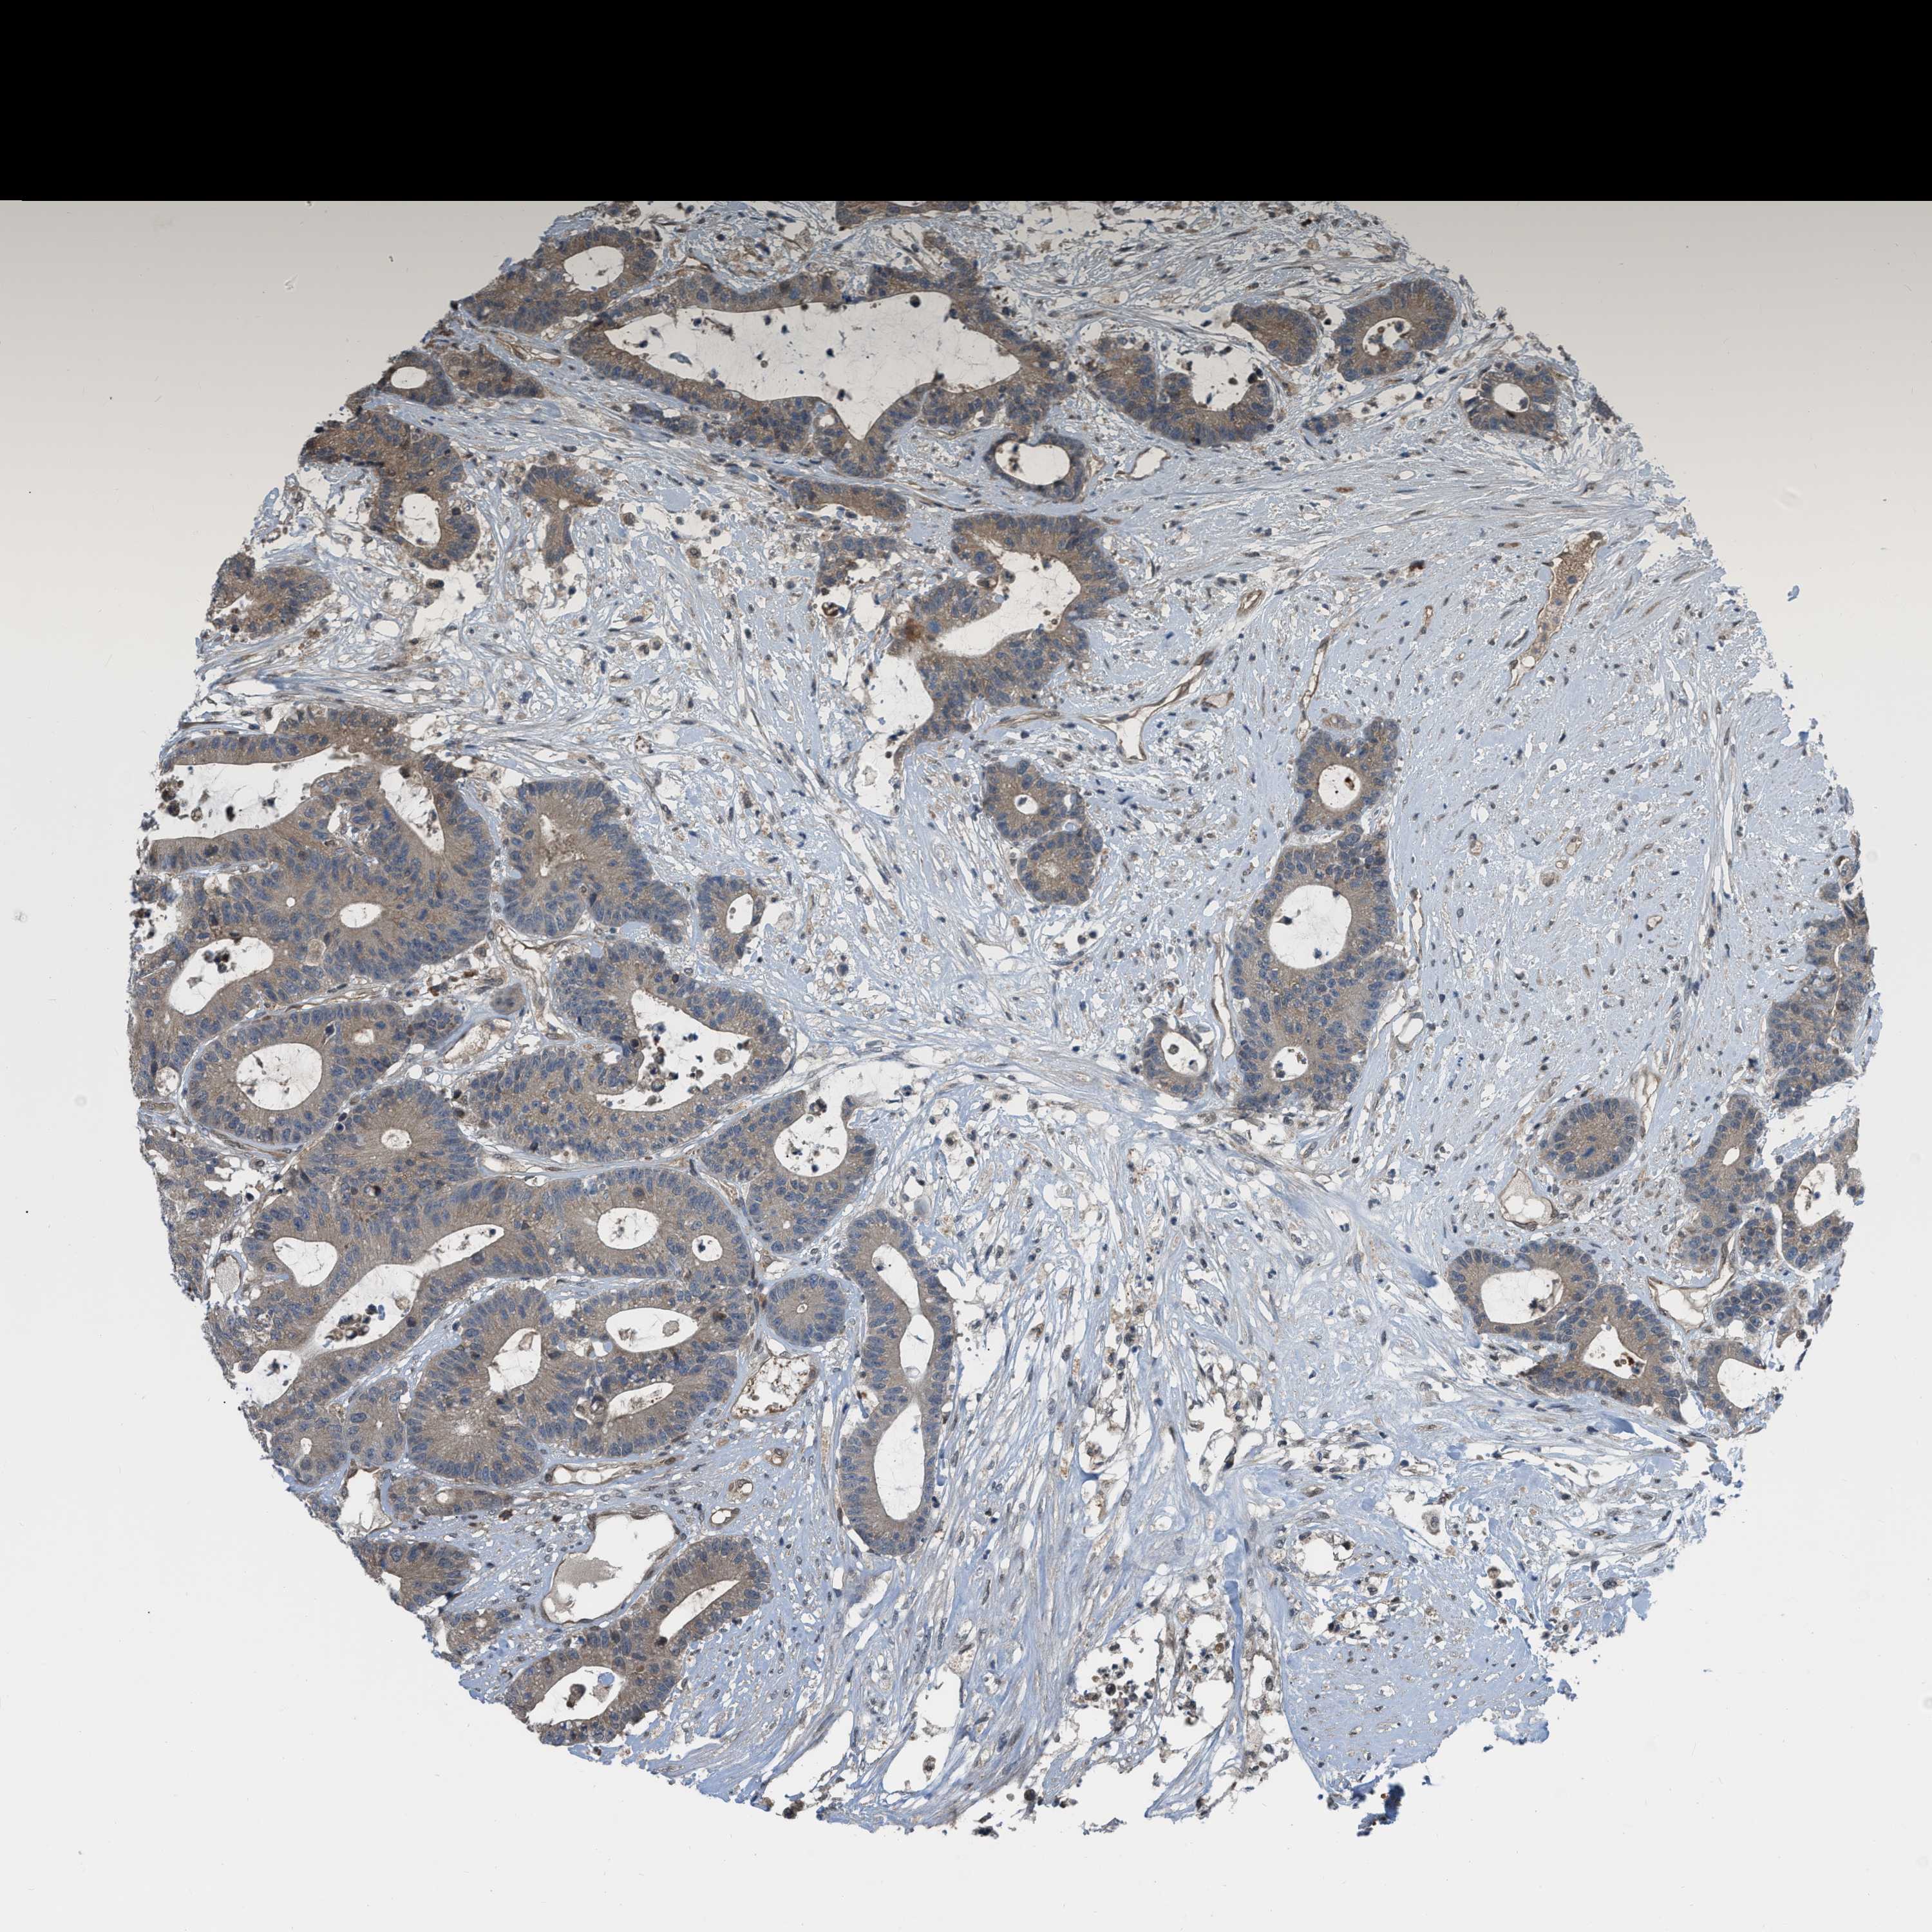

CANCER COLORECTAL CANCER Show tissue menu

Colorectal cancer

Colon adenocarcinoma